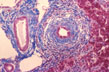

Fig 11 - SEPTAL BILE DUCTS

Located in the septal spaces at the confluence of few, 3-4, interlobular ducts are larger ducts measuring greater than 100 mu in diameter. They are normally surrounded by a concentric cuff of connective tissue and elastic fibers.